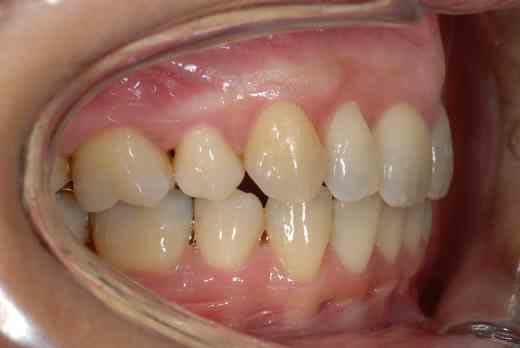

3 mois de mini vis et d'élastocs de classe II :-))

chuis pas belle comme ça? :-)))